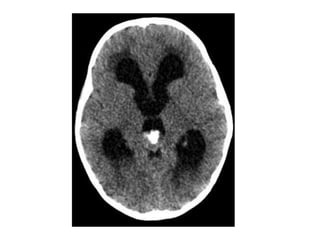

b) Pineoblastoma :

-Highly malignant PNET (Primitive Neuroectodermal

Tumors)

-In patients with trilateral retinoblastoma, Pineoblastoma

may develop in patients with familial and or bilateral

retinoblastoma

-(Exploded calcifications) along outside of mass

(peripherally), unlike germinoma which engulfs and

induces calcification of the pineal gland

-Dense enhancement

-Larger, more heterogeneous with much greater

propensity for local invasion and CNS dissemination

Axial nonenhanced CT shows a large pineal region mass with resultant hydrocephalus ,

the pineal calcifications are exploded toward the periphery (arrows)

Axial nonenhanced CTshows a large pineal region mass with resultant hydrocephalus , the pineal calcifications are exploded toward the periphery (arrows)